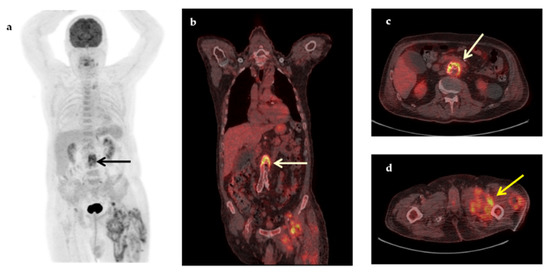

| Non-infectious Inflammatory diseases (NIID) | 11 (22%) |

| Large vessel vasculitis/Takayasu’s arteritis | 3 |

| Adult-onset Still’s disease | 2 |

| Sarcoidosis | 1 |

| Polymyalgia rheumatica | 1 |

| Inflammatory bowel disease | 1 |

| Familial Mediterranean fever | 1 |

| Neo-esophagus inflammation from gastroesophageal reflux | 1 |

| Subacute thyroiditis | 1 |